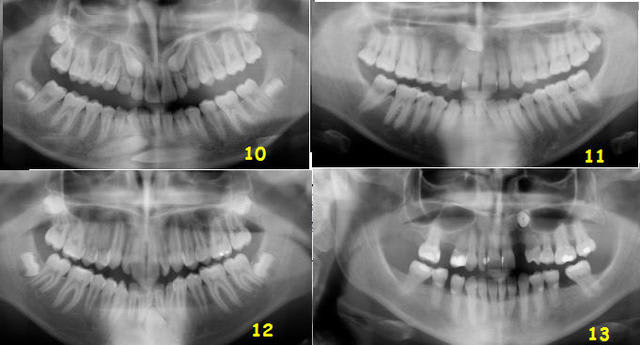

Et les autres, de 10 à 13 ?

Test canines suite et fin ljwpc0 - Eugenol

12: 33 L

13: couronne en V et apex en L ( si c'est l'inverse... c'est vraiment pas gagné )

pour les autres je ne suis pas encore décidée!!!

10: vestivulaires...toutes!!!

12: linguale

hum hum... et la n°11 ?

Daniel

couronnne en mésio vestibulaire et apex en disto lingual...j'ai bon m'sieur???

4 sur 7.

C'est pas mal, c'est plus que la moyenne.

Qui dit mieux ?